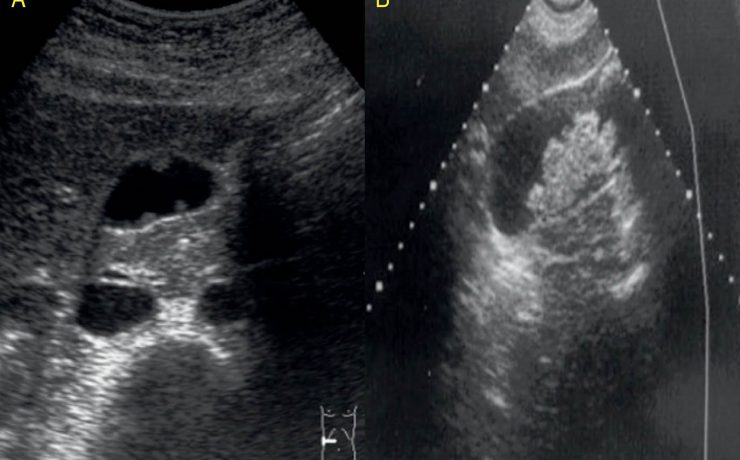

Cáncer de vesícula biliar

El cáncer de vesícula es poco frecuente por lo que no se incluye en importantes bases de datos internacionales de cáncer del mundo. No obstante su mortalidad es muy elevada por lo que realizar el diagnostico precoz se ha convertido en una necesidad imperiosa si de prolongar o salvar la